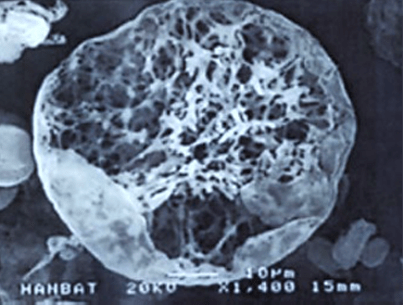

< 다공성 원형구조 미세분자 >

쥬베룩의 입자 형태

크기가 굉장히 작고 둥글기 때문에

결절이 잘 생기지 않고

생분해성으로 체외로 모두 배출되기 때문에

체내에 잔존물이 거의 남지 않습니다.

둥글게 생긴 다공성 망상구조의 입자가

콜라겐 재생효과를 비교적 오래 유지